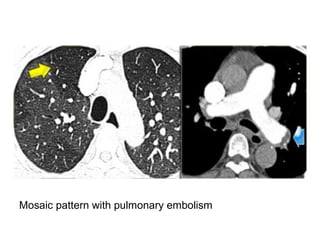

Mosaic pattern with pulmonary embolism

-Occluded contracted left

lower lobe pulmonary

artery (arrowhead) , there

is decrease in lung

attenuation of left lower

and right upper lobes and

more normally perfused

lung contributes to

mosaic pattern of lung

attenuation (arrows) ,

incidental note is made of

centrilobular emphysema